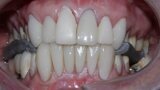

Figure 3 Anterior guidance before treatment